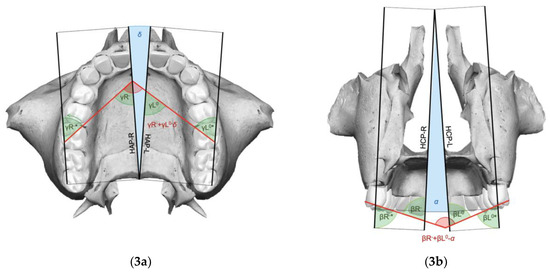

- For clinical improvements to be achieved in the expansion phase, it is necessary that the molar rotation angle (γ) and the intermolar angle (β) at the end of expansion are less than the difference between the respective pre-treatment angle and the orthopedic expansion angle.

- It is possible to calculate expansion angles (α and δ) by a reliable and reproducible method, respecting radiation protection principles, without requiring post-expansion CBCT scans, with the following formulas:

| Orthopedic expansion angle on frontal view (α) | Angle corresponding to the pyramid-like splaying pattern of the post-expansion maxillary components, projected on the frontal view |

| Orthopedic expansion angle on axial view (δ) | Angle corresponding to the pyramid-like splaying pattern of the post-expansion maxillary components, projected on the axial view |

| Molar angle of rotation (γ) | Angle formed by the intersection of the lines passing over the tips of the MPC and the DBC of the right and left maxillary upper first molars |

| Right molar angle of rotation (γR) | Angle formed by the intersection of the line passing over the MPC and the DBC tips of the right maxillary upper first molar and the Ans-Pns segment |

| Left molar angle of rotation (γL) | Angle formed by the intersection of the line passing over the MPC and the DBC tips of the left maxillary upper first molar and the Ans-Pns segment |